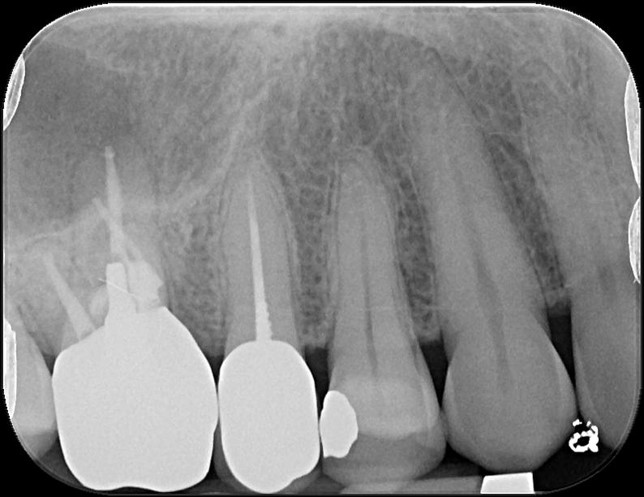

治療前,右上第一大臼齒疼痛

治療前,第一大臼齒根尖病變

顯微根管重治療